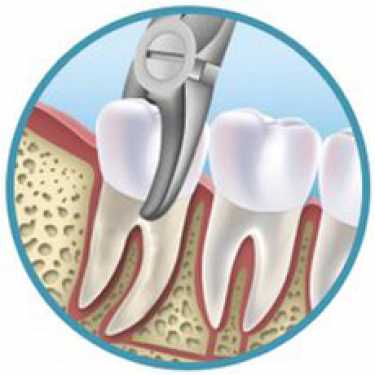

EXTRAÇÃO DENTAL

Quando os dentes estão muito destruídos e sem possibilidade de restauração, necessitam ser removidos.

Na extração simples, o dente é descolado do osso com um tipo de alavanca e então extraído com um fórceps dentário. A área é irrigada com soro fisiológico e finalmente fechada através de sutura.

Em extrações mais complexas, como as de dentes do siso e inclusos, é feita uma incisão na gengiva e uma parte de osso é removida, libertando a coroa do dente.

Esses procedimentos são feitos com um forte anestésico e para evitar dor e desconforto após a extração um analgésico é prescrito.